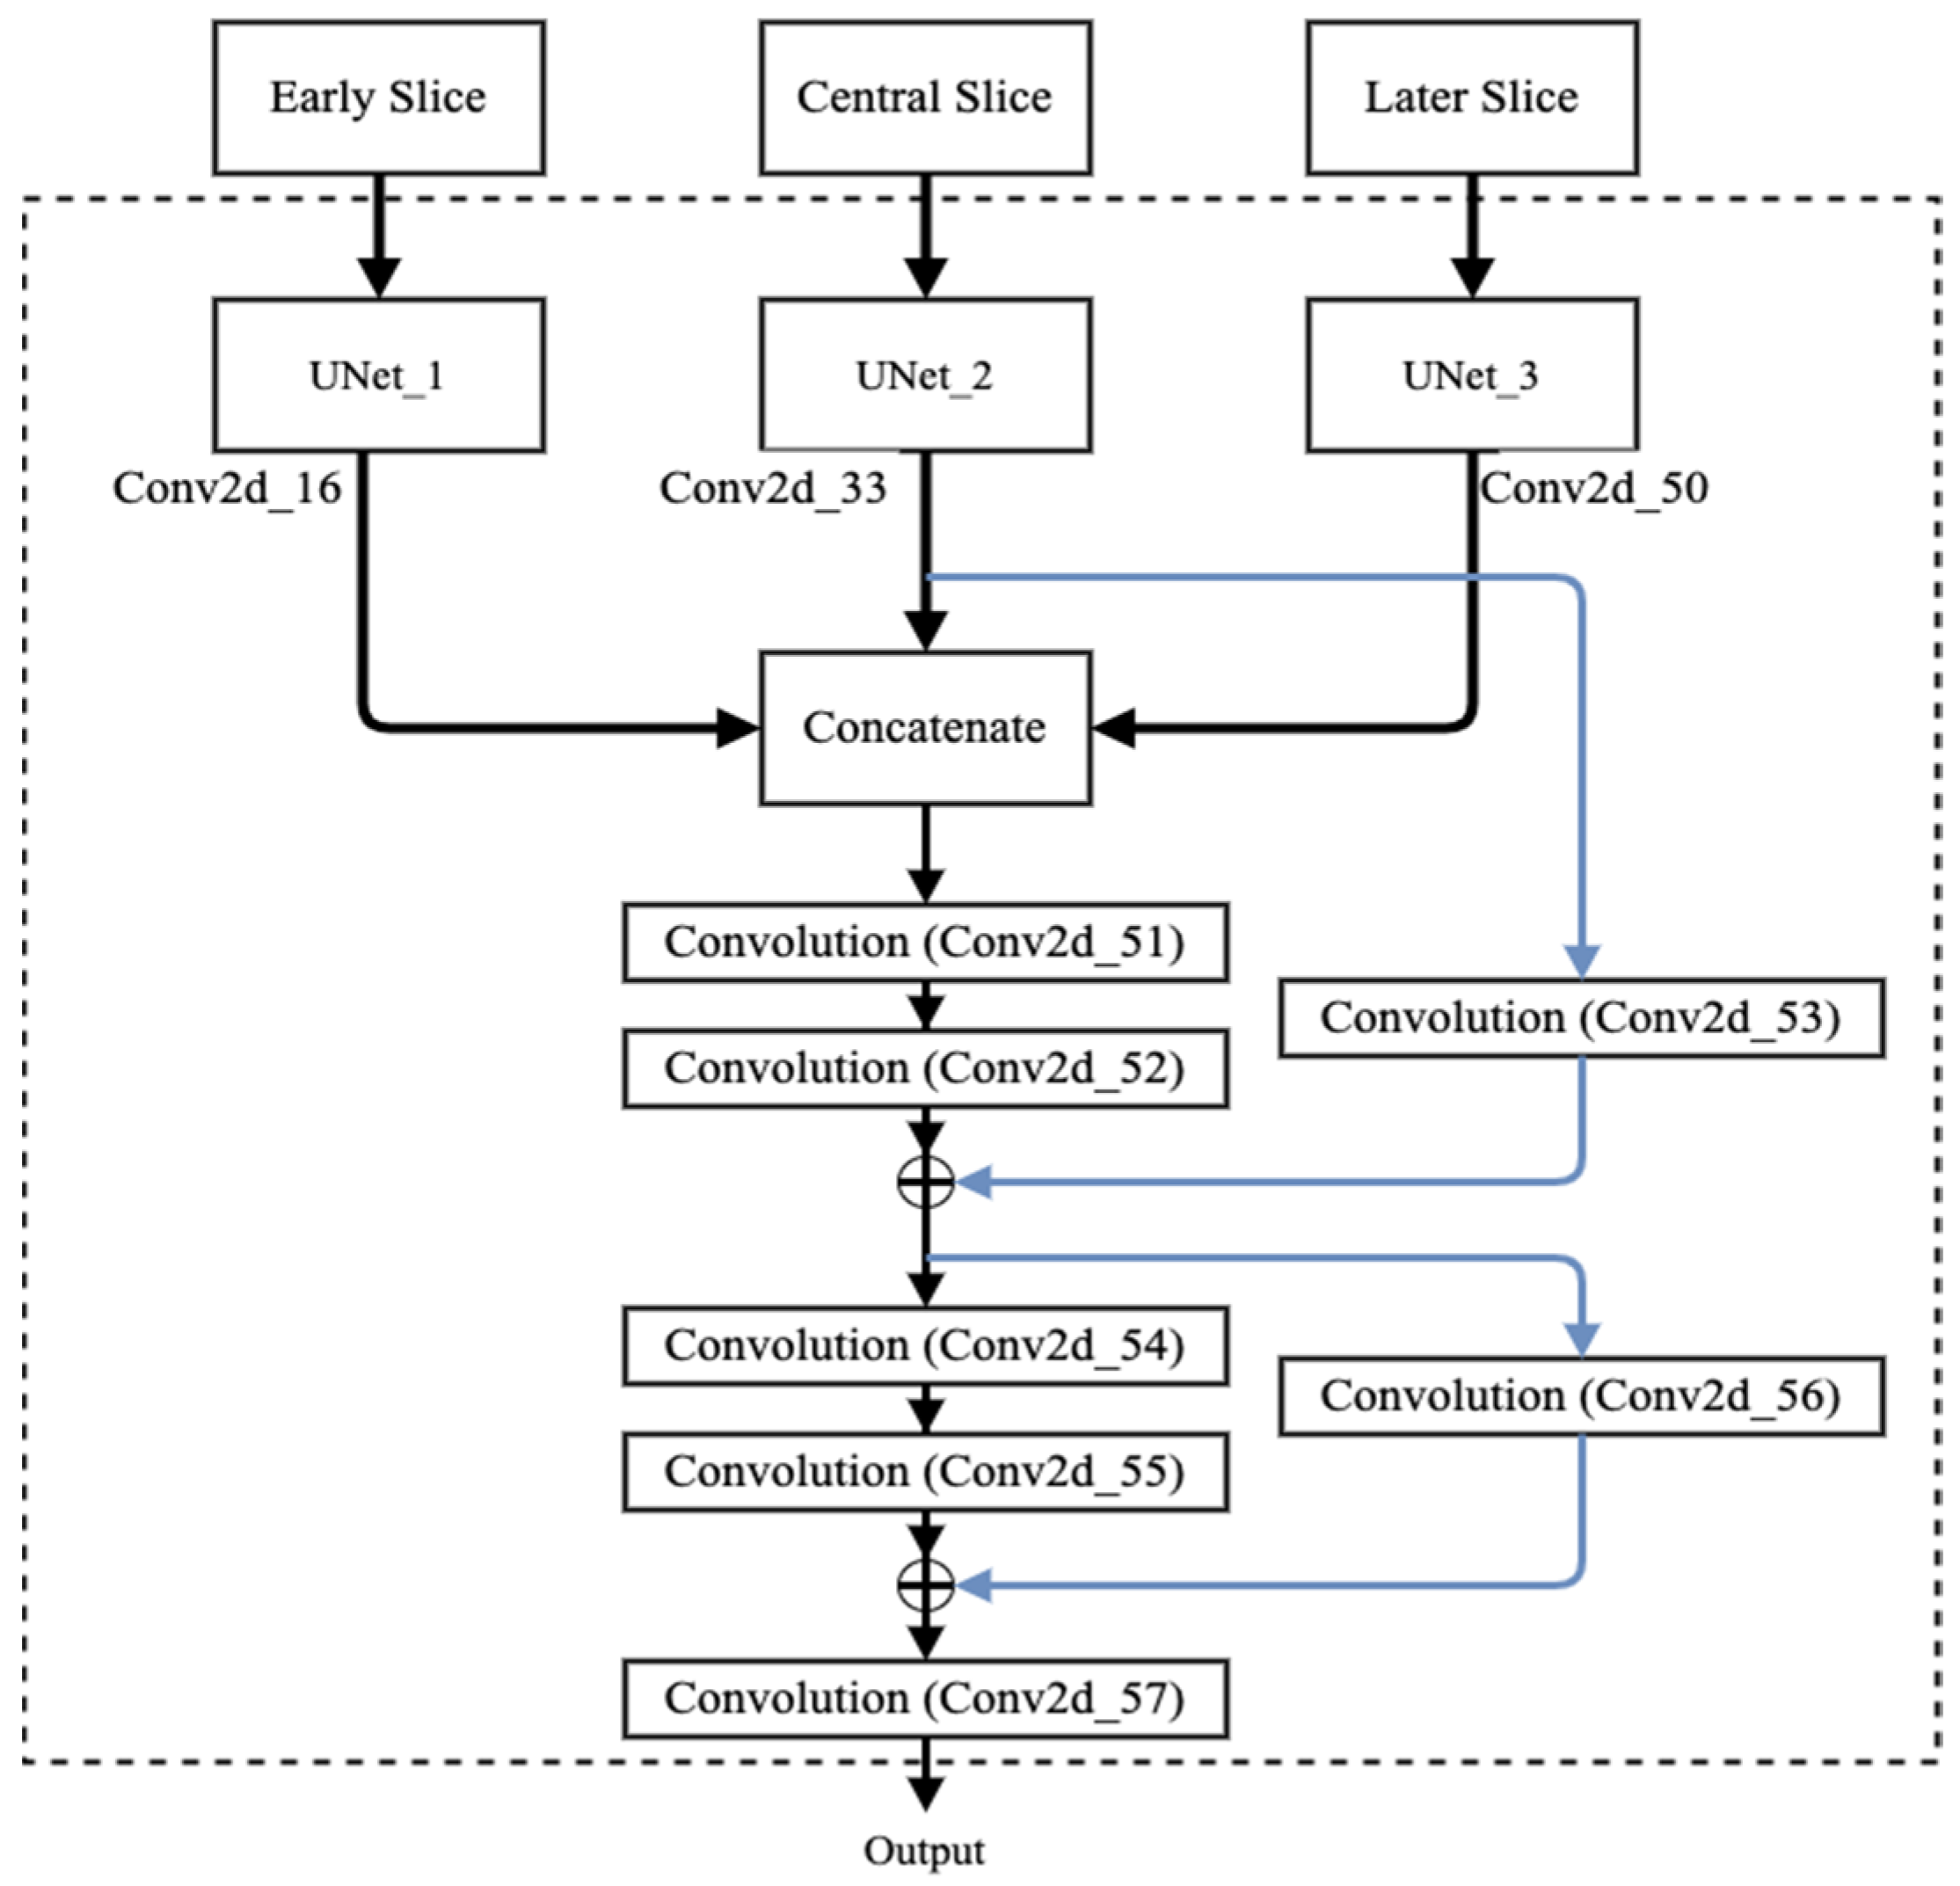

2.2.1. Parallel UNet

2.2.2. Proposed Fusion Using Residual Network

| Concatenate_12 | 256 × 256 × 96 | Conv2d_16, Conv2d_33, Conv2d_50 |

| Conv2d_51 | 256 × 256 × 64 | Concatenate_12 |

| Conv2d_52 | 256 × 256 × 64 | Conv2d_51 |

| Conv2d_53 | 256 × 256 × 64 | Conv2d_33 |

| Add | 256 × 256 × 64 | Conv2d_52, Conv2d_53 |

| Conv2d_54 | 256 × 256 × 32 | Add |

| Conv2d_55 | 256 × 256 × 32 | Conv2d_54 |

| Conv2d_56 | 256 × 256 × 32 | Add |

| Add_1 | 256 × 256 × 32 | Conv2d_55, Conv2d_56 |

| Conv2d_57 | 256 × 256 × 4 | Add_1 |